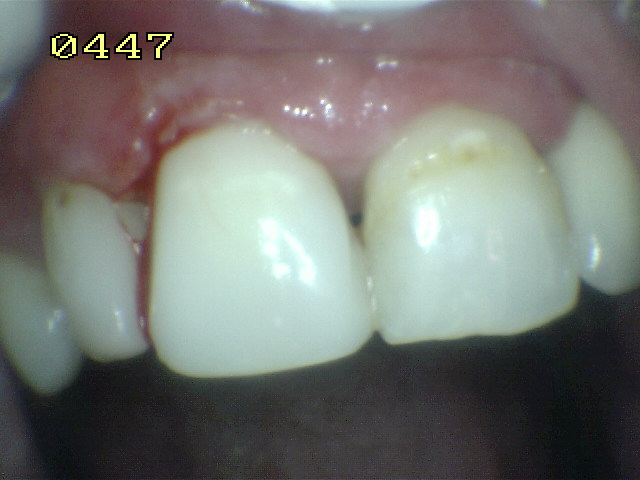

En 11 obturaciones de

clase 3 en mesial y distal con filtración marginal |

Se elimina el material y

tejido cariado, con un rebaje de la cara vestibular |